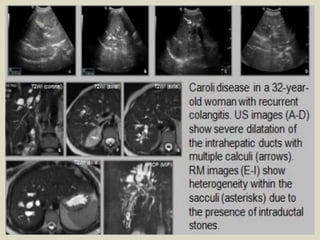

Mirizzi syndrome.

Mirizzi syndrome. a: Oblique coronal T2-weighted sequence. b: MRI cholangiography

with volume rendering. In this case, the presence of impacted gallstone in the cystic duct,

causing dilatation of the biliary tract and compression of the common hepatic duct.

Mirizzi syndrome. A 45-year-

old man presented with right

upper quadrant pain and

jaundice. Radial thick slab

MRCP image (A) demonstrates

cholelithiasis (short arrow),

dilated intrahepatic ducts and

common hepatic duct (block

arrow), but normal caliber of

the common bile duct (blue

arrow). There is a filling defect

at the insertion of the cystic

duct (long arrow). Axial single-

shot T2 TSE image (B) shows

an impacted stone (arrow) at

the insertion of the cystic duct

causing obstruction

of the common hepatic duct.